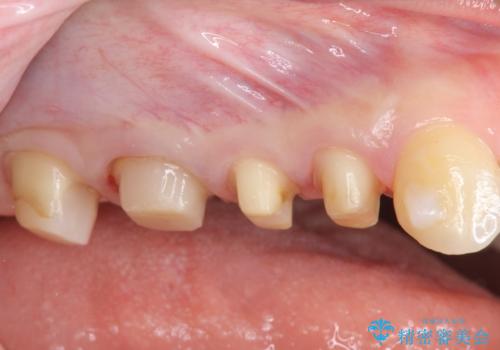

歯周外科を行い歯ぐきの整備を行うセラミック治療

- 歯の疼きや違和感、虫歯の治療を希望され来院されました。

銀歯周囲の虫歯再発や、歯ぐきよりも深い虫歯、根尖性歯周炎と言った複合的な問題を、

歯周外科、精密根管治療、セラミック治療を行い、妥協のないセラミック治療を計画します。

今回の治療では歯ぐきの問題を解決するため、歯周外科を行いました。